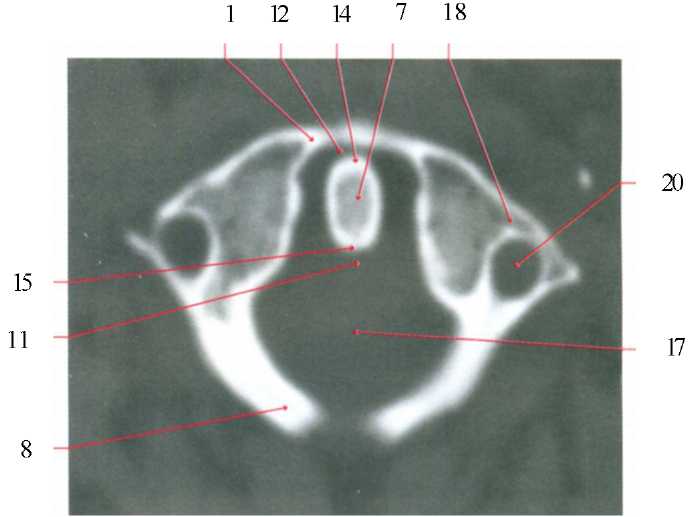

1) глазное яблоко; 2) хрусталик; 3) нижняя прямая мышца; 4) медиальная прямая мышца; 5) латеральная прямая мышца; 6) верхняя прямая мышца; 7) верхняя косая мышца; 8) нижняя косая мышца; 9) зрительный нерв; 10) зрительный канал; 11) глазничная щель; 12) слезная железа; 13) глазная вена; 14) передний наклоненный отросток; 15) петушиный гребень; 16) ретробульбарная клетчатка; 17) глазничная часть лобной кости; 18) клиновидная (основная) кость; 19) глазничная пластинка решетчатой кости; 20) нижняя стенка глазницы; 21) глазная артерия; 22) подглазничный канал; 23) подглазничный нерв; 24) мышца, поднимающая веко; 25) околобульбарная клетчатка; 26) верхняя челюсть; 27) глазничная поверхность верхней челюсти.

Аксиальная проекция

1) глазное яблоко; 4) медиальная прямая мышца; 5) латеральная прямая мышца; 7) верхняя косая мышца; 9) зрительный нерв; 11) глазничная щель; 12) слёзная железа; 13) глазная вена.